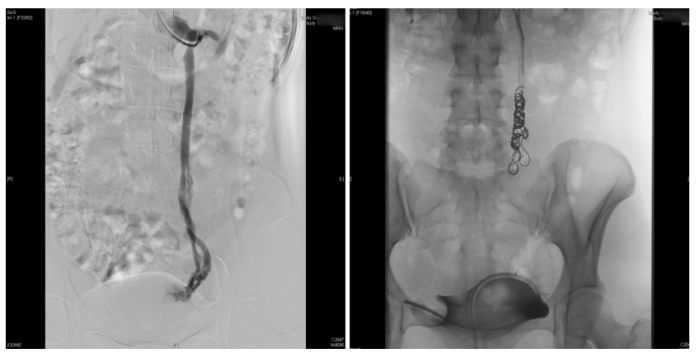

次日,赵扬程手术团队为她实施了卵巢静脉造影+栓塞硬化治疗术——一种微创介入手术,通过手臂头静脉穿刺,封堵异常迂曲粗大的卵巢静脉,终止血液反流。术后第三天,陈凡顺利出院,长期疼痛得到有效缓解。

术前(左侧卵巢静脉造影,造影剂返流至盆腔) 术后(弹簧圈+硬化剂治疗后造影,造影剂返流消失)